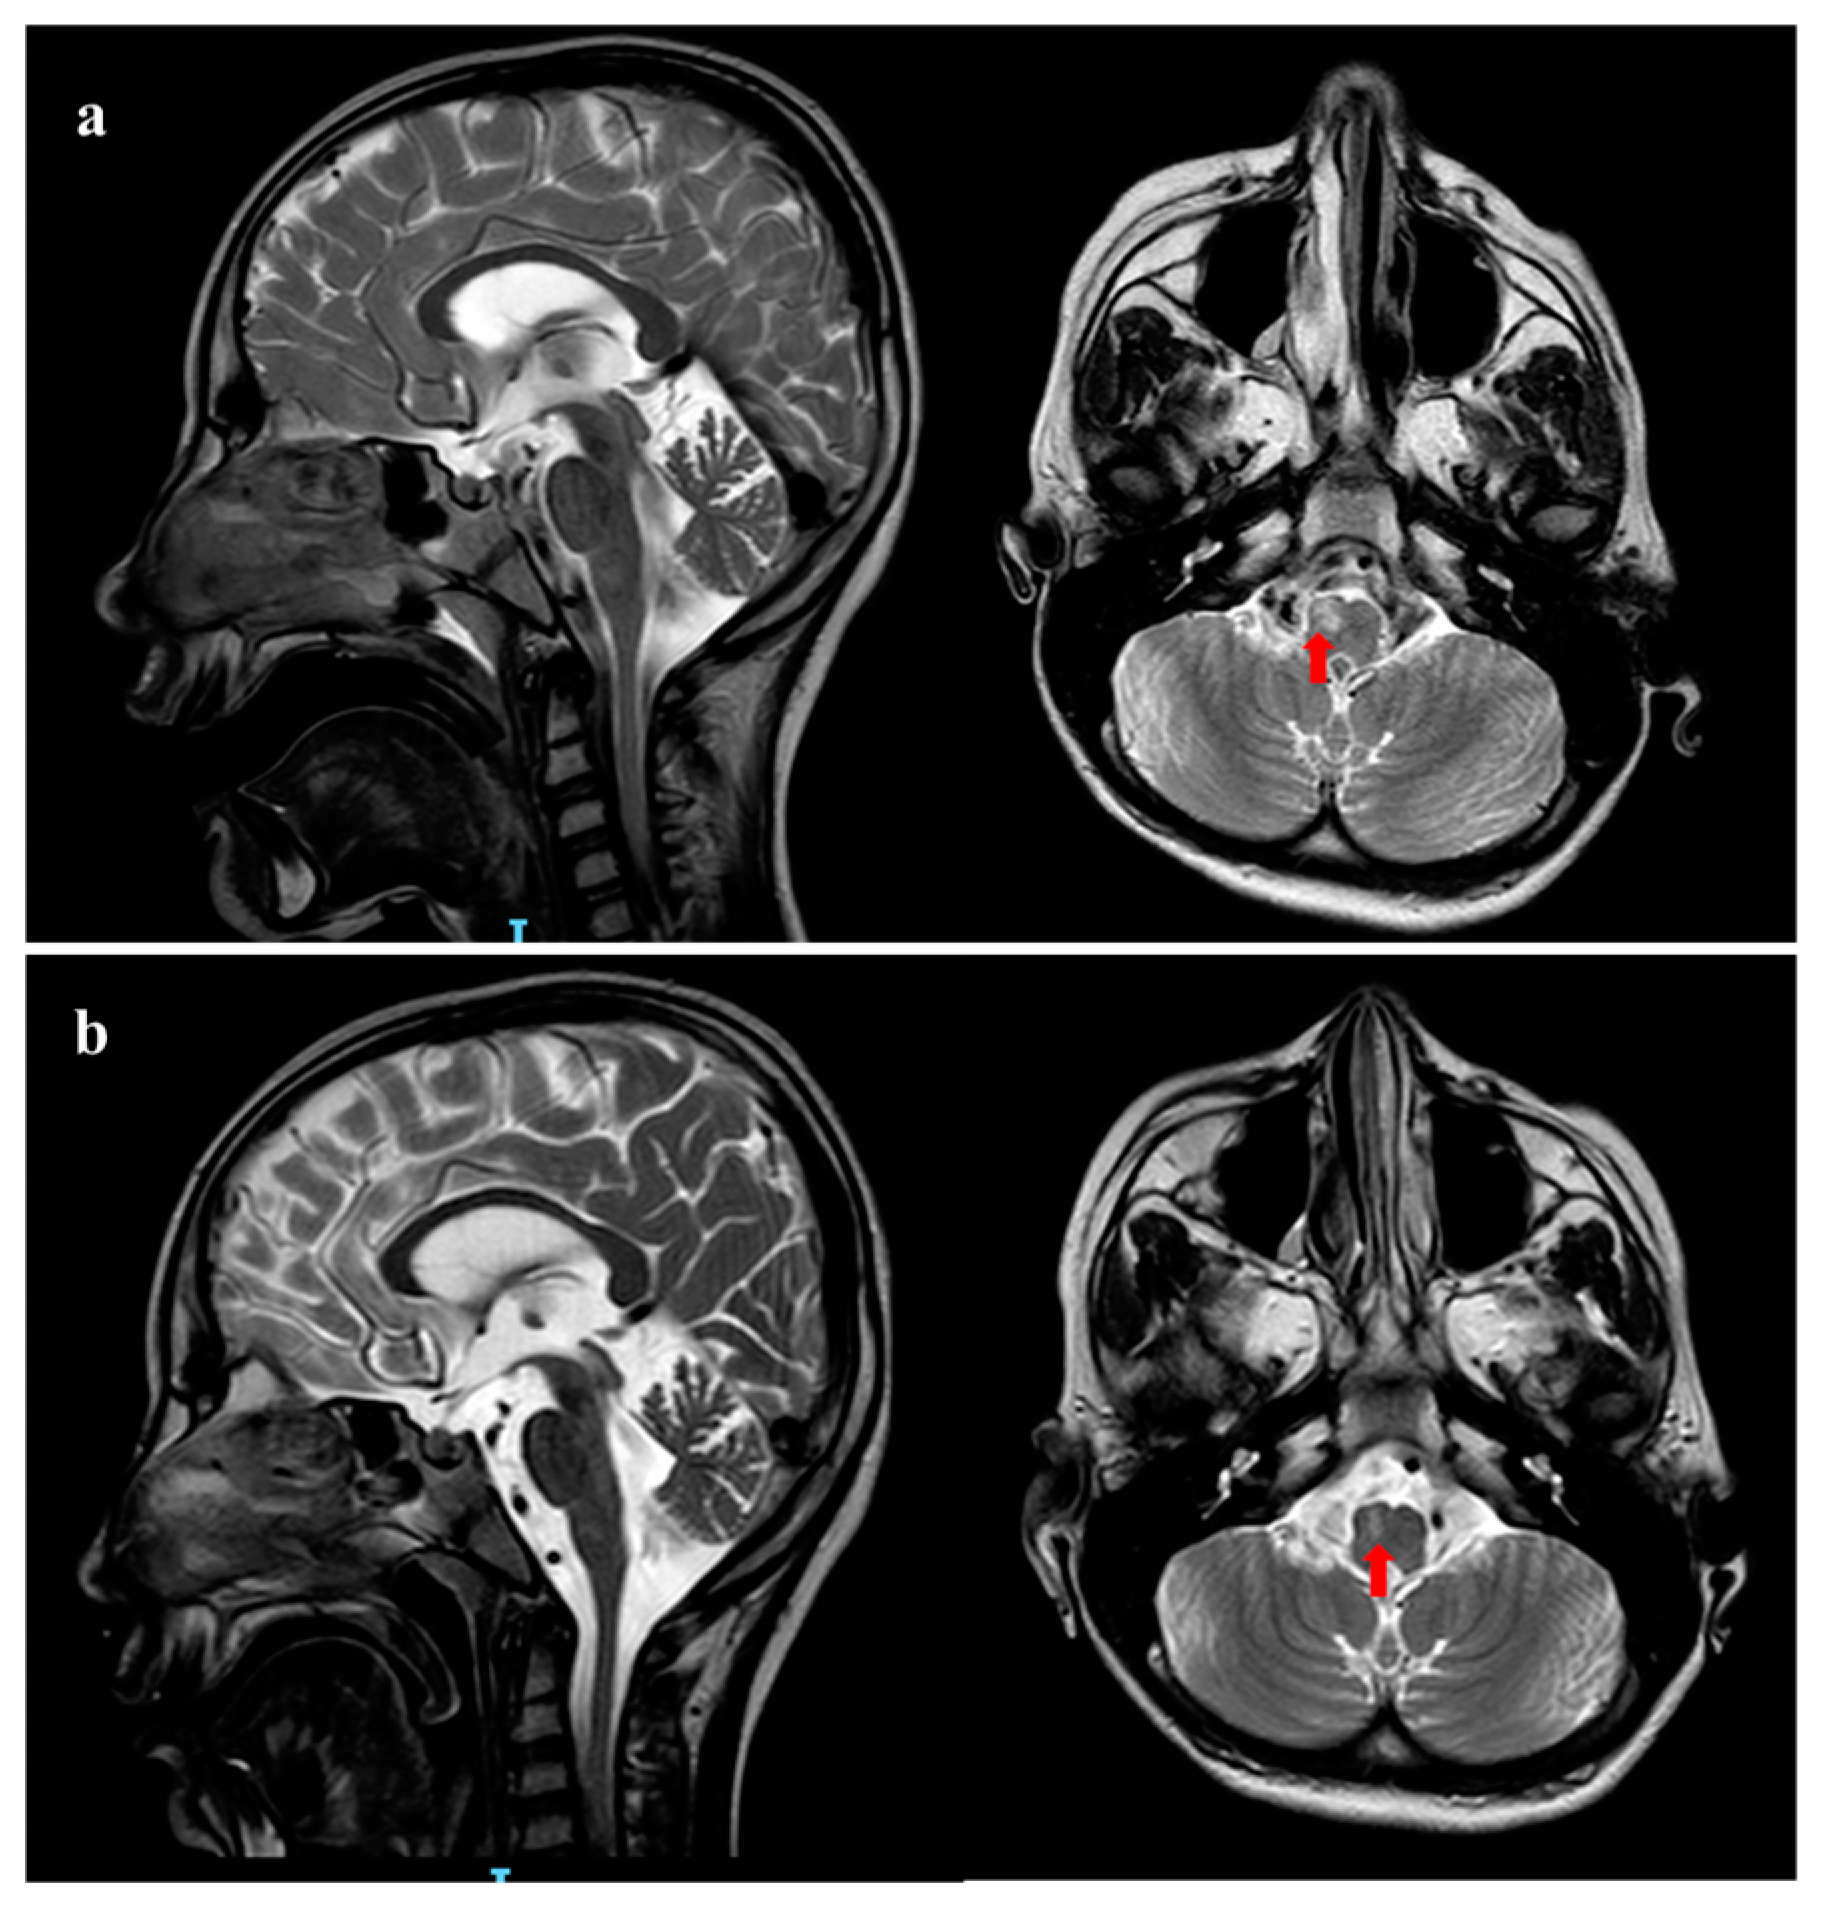

Due to the worsening of gastric symptoms, she was hospitalized at the age of 10 years. Brain MRI performed in acute phase revealed moderate global cerebral and cerebellar atrophy and T2-FLAIR (Flow-attenuated inversion recovery) hyperintensity of right bulbar pyramid with DWI restriction (Figure 1a), while MRI spectroscopy did not detect any lactate peak.

Figure 1. Brain MRI pattern. (a) Brain MRI performed in the acute phase at 10 years of age. Coronal and Sagittal T2 weighted images shows global cerebral and cerebellar atrophy. Red arrow shows hyperintensity of the right bulbar pyramid; (b) brain MRI performed 20 days later shows reduction in the right corresponding bulbar pyramid lesion.

During the follow-up, a worsening of the clinical picture occurred with refractory vomiting, respiratory failure and progressive neurologic degradation (GCS < 5). Prolonged EEG showed slowing background without a clear epileptiform activity; several AED therapies (continuous intravenous midazolam, levetiracetam, clonazepam) did not change either the clinical picture nor the electroencephalography (EEG) pattern. Blood tests for mitochondrial disorders (serum lactate and pyruvate) remained normal. A control brain MRI performed 20 days later showed moderate reduction in the right bulbar pyramid lesion without DWI restriction, suggesting ischemic origin (Figure 1b). After two months of hospitalization, the patient died from multisystem failure.